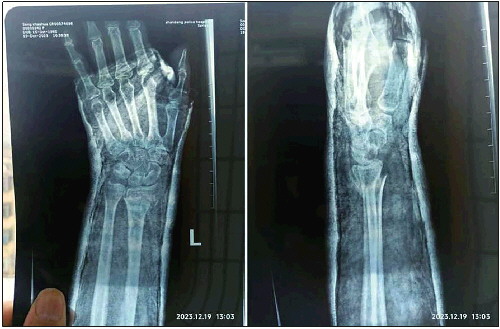

◥张秀梅上班途中滑倒,左手摔骨折。 受访者供图

2023年12月12日清晨,张秀梅(化名)像往常一样,骑着电动车赶往4公里外的单位,她是这里的一名保洁阿姨。熟悉的道路因头一天降下的雪变得非常滑,拐弯的时候张秀梅摔倒了,触地的左手传来一阵剧痛。随后,她被确诊为左手骨折,“自费将近两千元”进行了保守治疗——这些费用相当于她大半个月的薪资。而今,打着石膏的左手“完全不能动”,张秀梅在家调养,生活起居由丈夫照顾。